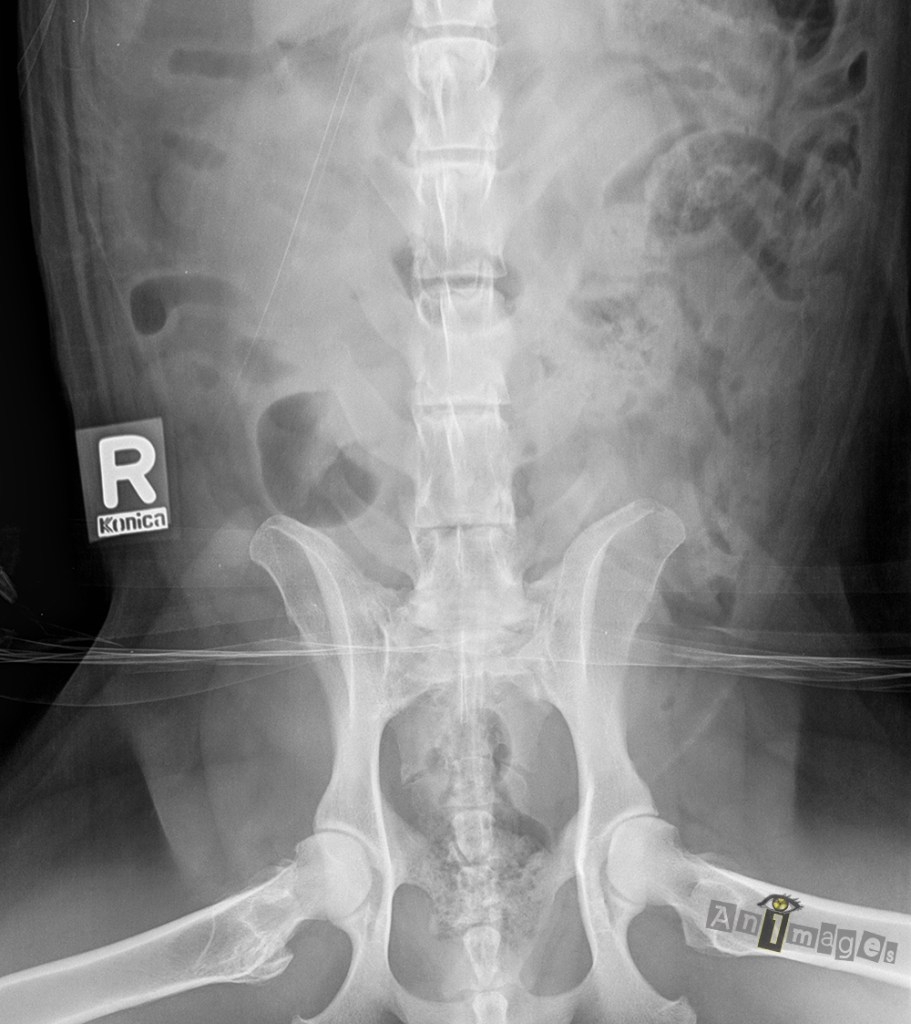

Ventrodorsale – caudale